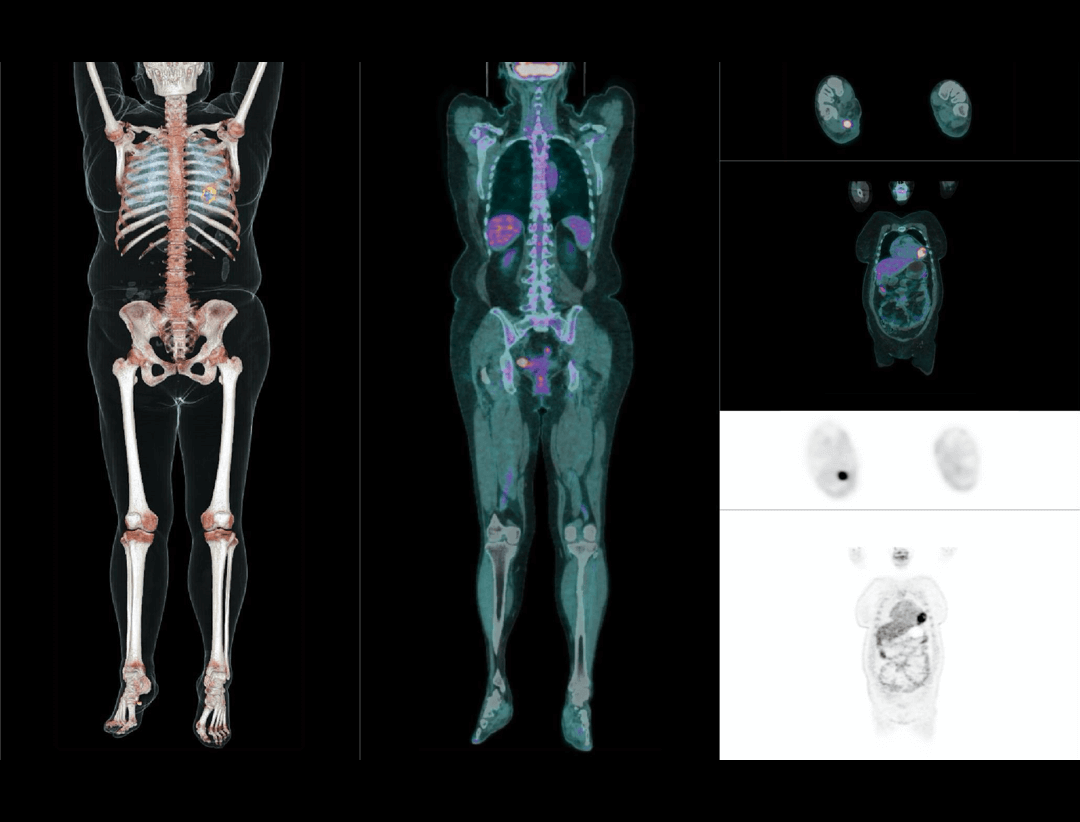

2.9mm

高いNEMA分解能。

TOF+PSF

分子イメージングの定義に革命を起こします。

600x600

画像の細部を可視化する高分解能イメージマトリクス。